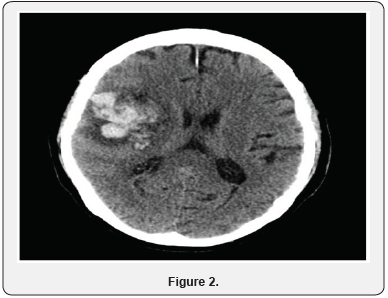

Initially patient was suspected to have meningitis and started on vancomycin, ampicillin, ceftriaxone and acyclovir. The antibiotics were stopped after HSV was confirmed and antiviral continued. On day 6 of hospitalization patient was noted to have decreased responsiveness. Patient had a Stat CT of the head which showed 5cm right temporal lobe hematoma with 3.5 mm midline shift to the Left (Figure 2). Neurosurgery was notified but it was determined that patient has a poor prognosis and is not a candidate for surgery. He was also transferred to intensive care due to respiratory distress and was intubated. The next day repeat CT of head showed increase in size of hematoma to 6 cm (Figure 3). Family decided to make the patient comfort care only and he was transferred to hospice.